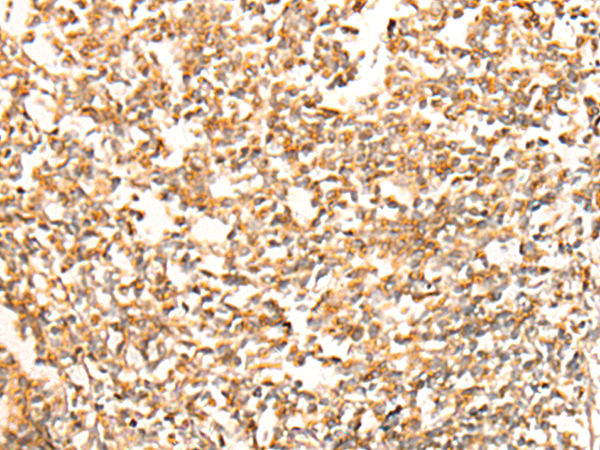

IHC positive control: |

Human liver cancer and Human tonsil |

IHC Recommend dilution: |

25-100 |